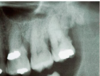

What is this radiographical finding?

Metastatic Carcinoma to Jaw Bones

C. Periapical image of a metastatic lesion of breast carcinoma; note the irregular widening of the periodontal membrane spaces and patchy sclerotic bone reaction, especially around the roots of the molars